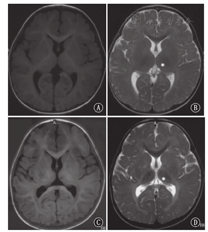

P1~P3于出生7~8个月起病,P4~P6于出生3个月内起病。P5生前即表现宫内发育迟缓,其余患儿均以发育里程碑延迟为首发症状。智力运动发育迟缓伴倒退见于所有患儿,P1~P3在1岁4个月~1岁6个月开始倒退,P4~P6为7~9个月。P2有眼震。P4在1岁6个月对外界声光刺激已无回应,余患儿常因声音诱发惊跳反应。4例(P2~P3、P5~P6)有癫痫史。患儿均出现饮水呛咳伴咀嚼功能减退导致喂养困难。6例患儿除P5外出生史及体格生长均无明显特殊,P5足月顺产,出生体质量2.25 kg,1岁1个月时头围43.5 cm,2岁6个月时身长85 cm,体质量11.5 kg。患儿均未见粗陋面容。6例仅P5行眼底检查,未见樱桃红斑。P4可见全身Mongolian斑及肝脏进行性肿大。5例(P1~P2、P4~P6)肌张力低,P3肌张力高,P3、P5肌张力不全(表1)。6例患儿仅P4于6月龄行X线骨关节检查,未发现骨骼畸形。6例患儿头颅MRI均见髓鞘化落后,4例(P2~P3、P5~P6)见T2加权像丘脑低信号,4例(P2~P4、P6)见大脑或小脑萎缩(图1)。

注:A:1岁6个月,T1加权像;B:1岁6个月,T2加权像;C:2岁8个月,T1加权像;D:2岁8个月,T2加权像

A:1 year and 6 months,T1W image;B:1 year and 6 months,T2W image;C:2 years and 8 months,T1W image;D:2 years and 8 months,T2W image

GM1神经节苷脂累积病头颅MRI可表现为大脑及小脑萎缩;白质T2加权像高信号,提示髓鞘形成不良;胼胝体发育不良;基底核及苍白球T2加权像低信号;壳核T2加权像高信号[15,16,17,18]。本组病例头颅MRI均可见髓鞘形成不良,部分病例可见脑萎缩、基底核或丘脑异常信号,符合GM1神经节苷脂累积病头颅MRI表现。